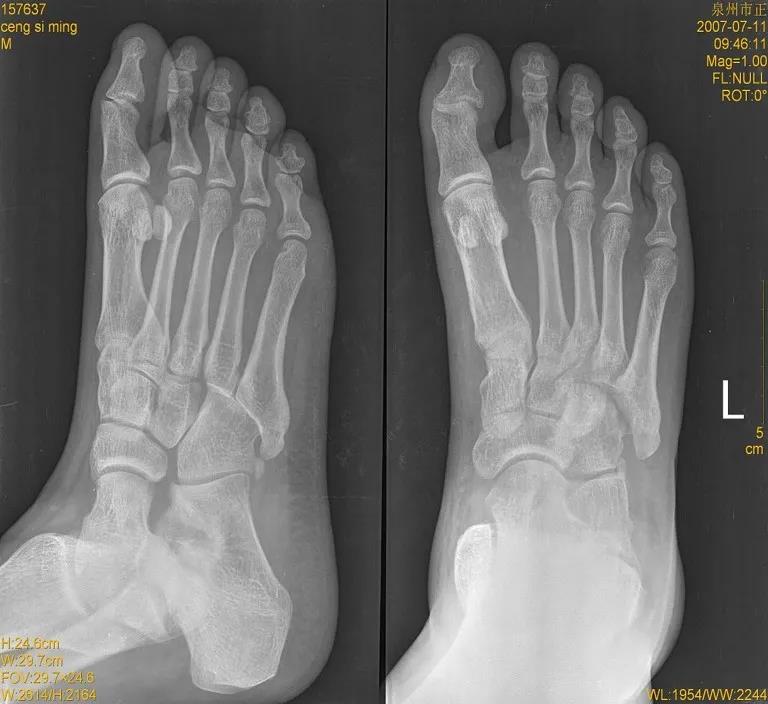

X线片:基本的辅助检查(应注意某些情况并非骨折)CT:能进一步检查隐匿性骨折或撕脱性骨折MRI:可检查肌腱、韧带的损伤肌骨超声:可代替或结合MRI检查软组织的损伤

X线